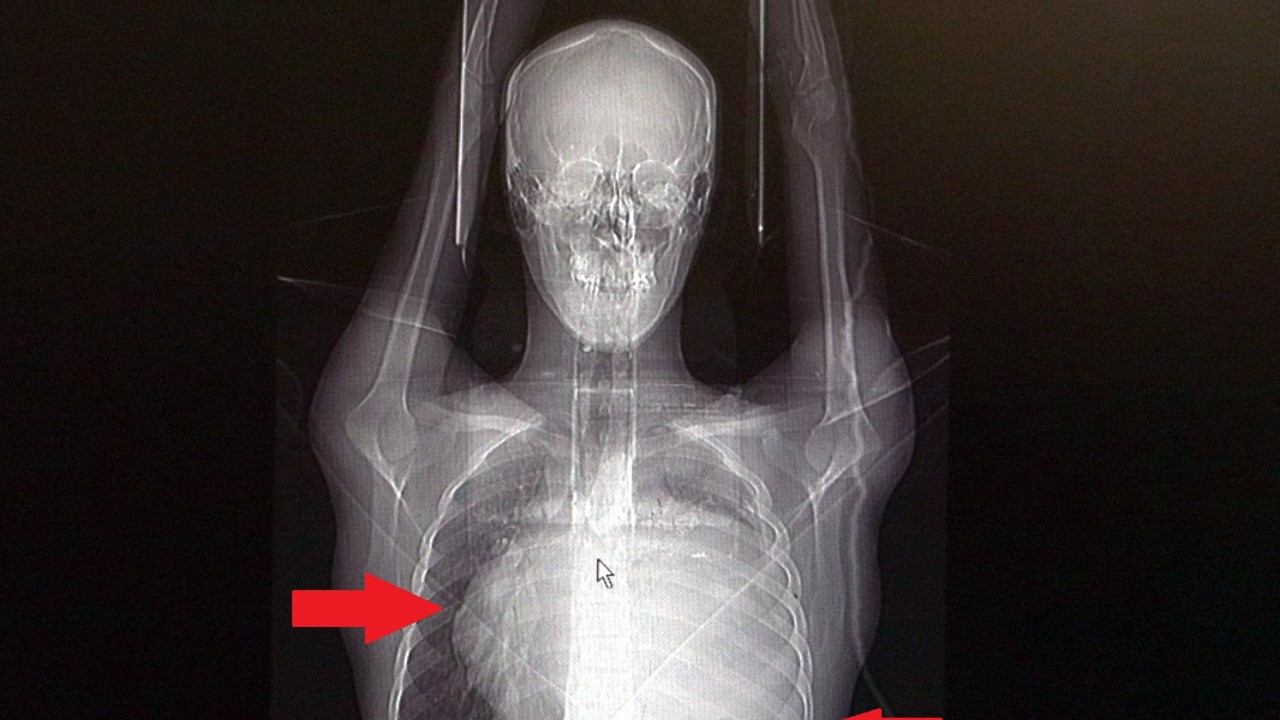

İstanbul’da yaşayan 21 yaşındaki Burak Aktaş, Temmuz ayında işe girmek üzere sağlık raporu almak için hastaneye gitti. Herşey yolundaydı ve raporunu alarak iş başı yaptı. Bir ay geçmeden nefes darlığı, halsizlik, öksürük gibi şikayetlerle başka bir hastaneye gittiğinde ise ilk şoku yaşadı. Sol göğüs boşluğunda portakal büyüklüğünde bir kitle tespit edilmişti. Yapılan biyopside tümörün akciğer kaynaklı olmadığı, henüz cenin aşamasında eşey hücrelerinin farklılaşmasıyla gelişen “immatür teratom" teşhisi kondu. Kitleyi küçültmek için kemoterapi uygulansa da tam tersine tümör 2 ay içinde neredeyse 10 katına çıktı ve büyük bir karpuz boyutuna ulaştı. Sol akciğerinin yüzde seksenini kağıt gibi ezen, kalbini göğüs duvarında 12 santim sağa kaydıran ve hem kalbe hem beyne giden ana damarlara baskı yapan 6.5 kilo ağırlığındaki dev tümör, Koşuyolu Yüksek İhtisas Eğitim ve Araştırma Hastanesi Göğüs ve Kalp Damar Cerrahisi ekiplerinin birlikte girdiği operasyonla başarılı şekilde çıkarıldı. Operasyon sırasında Aktaş’ın kalbi normal yerine çekildi, sol akciğerin üst lobu alındı, ezilen alt lobu ise anestezi ekipleri tarafından pozitif basınçla yeniden şişirildi. Ameliyatı gerçekleştiren ekipten Prof. Dr. Erdal Taşçı, Aktaş’ın göğüs boşluğunun neredeyse tamamını kaplayan 6,5 kiloluk tümörün teratom (eski Yunancada ‘canavar tümör’) türlerinden biri olduğunu ve embriyonik hücrelerden kaynaklandığını kaydetti.

Prof. Dr. Erdal Taşçı, "Bundan 2,5-3 ay öncesine kadar hiçbir problemi olmayan, hayatını normal devam ettiren bir delikanlı Burak. Göğüs ağrısı öksürük ve nefes darlığı şikayetiyle sağlık kuruluşuna başvuruyor. Orada yapılan tetkiklerinde sol göğüs boşluğunda akciğerinden kaynaklanmayan portakal büyüklüğünde bir kitle tespit ediliyor ve immatür teratom tanısı konuyor. 2 ay arayla yapılan tetkiklerinde ve arada cerrahi öncesi küçültme amaçlı kemoterapi almasına rağmen, portakal büyüklüğündeki tümör, irice bir karpuz büyüklüğüne, yaklaşık 6 kilo 300 grama kadar ulaşıyor. Göğüs boşluğunda kemik kafesi içinde olduğu için, itebileceği iki organ var; biri kalp, diğeri de akciğerler. Soldan sağa doğru büyüdüğü için kalbi tamamen göğüs boşluğunun sağ tarafına itmiş ve kalbe giren ve kalpten çıkan bütün büyük damarları da yer değiştirmenin etkisiyle bükülmüş durumdaydı. Bu nedenle vücuduna yeterince kan gitmiyordu. Ağustos ayının başında portakal büyüklüğündeyken kitle Eylül sonuna irice bir kavun, Ekim ayına geldiğimizde ise bir karpuz büyüklüğüne ulaştığı için, kitlenin büyüme hızı bizi acilen ameliyat yapmaya yöneltti. Yaklaşık 8-10 kat hacimsel olarak artmıştı. Sol akciğer tamamen ezilmiş ve kağıt haldeydi, alt lobu anestezi ekibimiz yüksek basınç uygulayarak tekrar şişirdi. Çok fazla vaktimiz yoktu, kitle basısından dolayı yaşamla bağdaşmayacağından dolayı hızlı hareket etmek zorundaydık. Bize geldikten üç gün sonra hemen ameliyata aldık çünkü tümörden ziyade onun yaptığı baskıdan kaynaklı hayati riski vardı" dedi.

Normalde kalbin özellikle alt ucunun göğüs boşluğunda, iman tahtası orta çizgi kabul edilirse, sola bakar şekilde durduğuna dikkat çeken Prof. Dr. Taşçı, sözlerini şöyle sürdürdü: "Ama bu hastada yaklaşık 12-13 s santimlik kalbin alt ucununu yer değiştirmesi ve kalbe giren çıkan bütün damarlar bükülüp kan akımı bozulmuştu. Kalp Damar Cerrahisi ekibi de bizimle beraber ameliyata girdi. Sol akciğerin üst lobu artık geri dönüşümsüz olarak ezildiği için çıkarmak zorunda kaldık. Kalbi tekrar eski pozisyonuna getirdik. Ameliyat sonrası çok çabuk toparladı. Koşuyolu ailesi olarak böyle büyük bir vakanın altından başarıyla çıktığımız için de ayrıca çok gururluyuz. Bundan sonra onkolog arkadaşlarımız hastamızın yaşamına çok olumlu dokunuşlar yapacak. İmmatür teratom genelde embriyojenik çağda gelişim gösteren germ hücrelerinin farklılaşmasıyla büyür. Vücudun herhangi bir yerinde gelişebilir ve içinde saç, diş, kemik artıkları, jölemsi kıvamda maddeler bulundurabilen bir tümör çeşididir. Kombine tedavilerde çok iyi sonuçlar alınıyor. Bu çocuğumuzu ileride güzel bir hayat bekliyor."